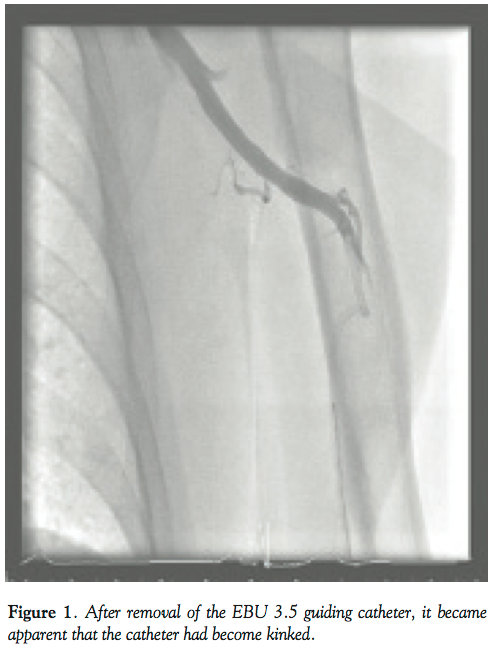

An 86-year-old male with diabetes, hypertension, and peripheral vascular disease presented to our institution with non-ST elevation myocardial infarction (NSTEMI). Coronary angiography performed by the left radial approach demonstrated a severe lesion in the mid left circumflex (LCX) artery and a further lesion in the mid left anterior descending (LAD) artery. Both lesions were successfully treated with percutaneous intervention with the use of bare-metal stents (3.5 x 15 mm in LCX, 3.0 x 28 mm in LAD) with excellent angiographic outcomes. On removal of the EBU 3.5 guiding catheter (Cordis Corporation), it became apparent that the catheter had become kinked (Figure 1) and was unable to be untwisted using conventional techniques involving guide catheter manipulation, the standard 0.035˝ guidewire, a super-stiff wire, and gentle rotation. Despite multiple attempts at unraveling the catheter, it could not be removed through the left radial access point and the patient experienced considerable discomfort with each manipulation.

We elected to convert to a right femoral approach with a view to rescue the kinked catheter with use of a vascular snare. However, due to a lack of an available appropriately-sized snare and concerns with the use of a large-caliber sheath in an octogenarian with peripheral vascular disease, we explored other options. We elected to use a novel balloon retrieval technique. A 6 Fr JR4 guide was used to enter the left subclavian artery and manipulated to lie within close proximity of the kinked EBU 3.5 catheter. A Whisper MS wire was advanced through the JR4 guide in an attempt to enter the distal end of the kinked guide catheter (Figure 2). Eventually, the Whisper wire passed into the kinked catheter and was manipulated into the proximal limb of the kinked guide. A 3.0 x 15 mm NC balloon was then passed through the JR4 guide over the guidewire into the distal end of the kinked guiding catheter. The balloon was inflated to 16 atm and gentle backward traction was applied to the JR4 guide (Figure 3). Eventually, both the JR4 guide and the kinked catheter were brought back to the ascending aorta (Figure 4). The catheter was untwisted using the JR4/balloon system that enabled controlled manipulation in the ascending aorta, enabling the EBU 3.5 guide to be removed from the left radial sheath with the use of a standard 0.035˝ wire. Following the procedure, the patient had a good radial pulse without complication.